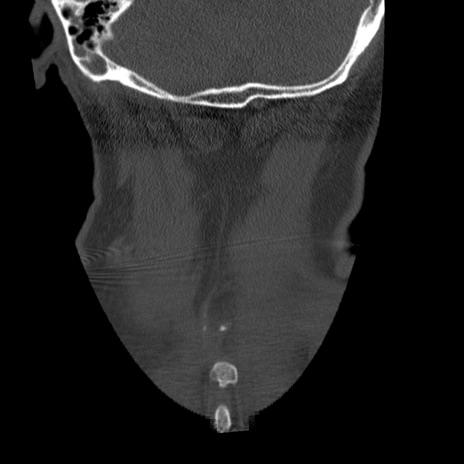

症例50 頚椎CT(冠状断像)

【症例】60歳代女性

【主訴】後頭部〜右後頸部にかけての痛み

【現病歴】本日飲食店でコーヒーを飲んでいたところ、突然後頭部〜右後頸部にかけて痛みが出現し、右上肢の感覚障害を伴ったため救急要請。

【身体所見】脳神経学的に明らかな異常所見を認めず。右上肢に軽度の感覚障害あり。

異常所見と診断は?

矢状断像